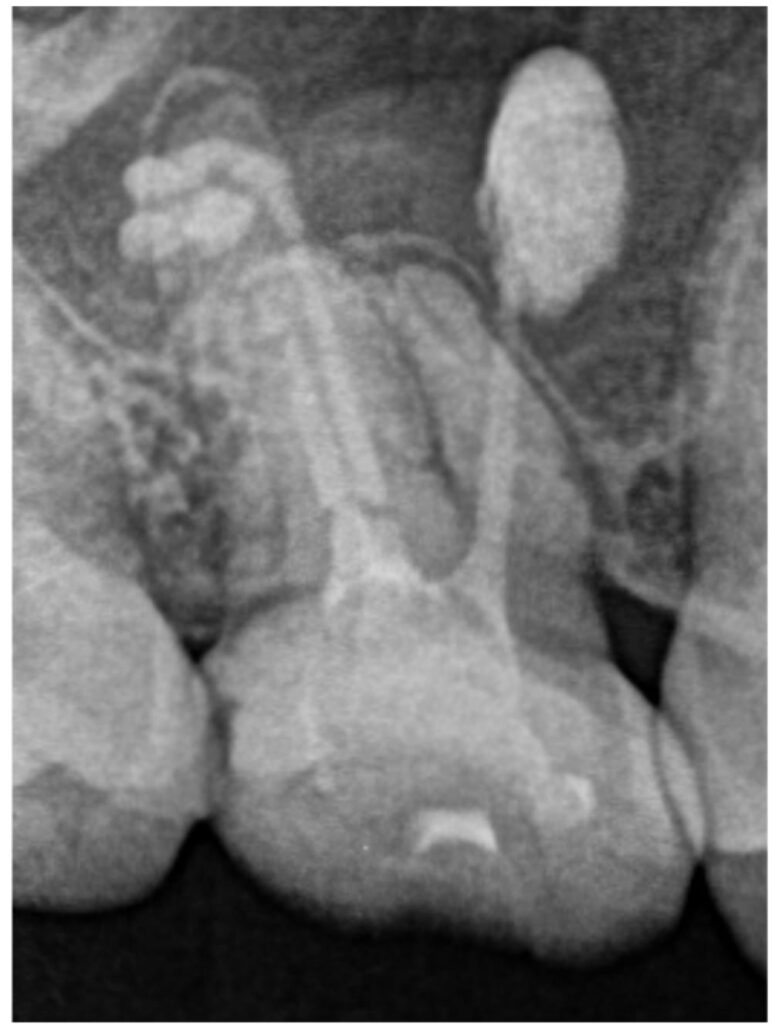

右上6番は、近心根管のパーフォレーション(穿孔)が疑われ、そこから根尖孔外へレントゲン的に白く写る不透過性物質の押し出しが確認できました。性状から、貼薬材料あるいは根管充填に使用するシーラーであると推測されました。

もともとラバーダムなしで根管治療が行われていたことから、根管内の細菌感染が疑われる状態であったため、まずは通常通りの非外科的な根管治療を行い、治癒しない場合に外科的歯内療法へ移行することになりました。

精密根管治療

根管内の古い詰め物をすべて除去し、本来の異なる方向に穴があいているパーフォレーション部位に対しては、MTAセメントを使用して穿孔封鎖を行いました。

治療は2回で完了し、飛び出ている材料の状態も含め、経過観察となりました。